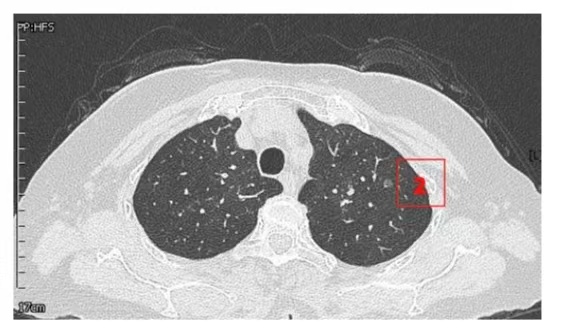

患者女性,71岁,因“发现左肺多发结节2周”入院。胸部CT提示左肺多发磨玻璃结节,较大者位于左肺上叶,呈类圆形,边界清晰,最大直径约9mm。该CT表现高度提示恶性可能。鉴于患者结节数量较多,为减少术中肺组织损伤,术前于CT引导下行经皮肺结节定位术,继而实施胸腔镜下左肺楔形切除术。术中共切除肺部结节6枚。术后病理示:左肺上叶较大结节(4号)为微浸润腺癌,其余5枚结节均为原位癌。患者术后恢复良好,于术后第1天拔除胸腔引流管,第4天顺利出院。

▲定位操作